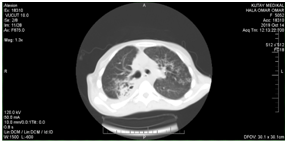

Female Patient (PT) 15 years old, referred to our hospital after more than 6 months of recurrent infections in right lower lobe (RLL) of the lung Figure A1 & A2. The PT had investigated, CXR was done Figure A3. The sputum was negative for TB many times. Bronchoscopy was done, no foreign body, no tumor, no anomalies, the washing was tested for TB and was negative. The decision for surgery was taken, the RLL was contracted, nodular and solid. RL Lobectomy was done. At second day post operation the PT had fever, sweat, no appetite and bad general condition. CXR revealed bilateral diffuse infiltrations. Figure B1. We decided to give her a trial TB treatment. After five days PT began to respond clinically. So TB treatment for minimum 6months is ordered.

A1 22-1-2019

A2 6-2-2019

A3 19-6-2019